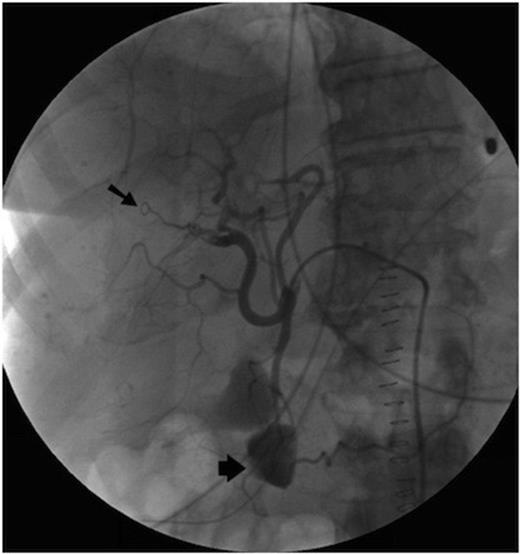

Post operatively the upper gastrointestinal bleeding continued. A second urgent OGD endoscopy showed more blood clots and fresh blood in the fundus, but once again no source for the bleeding was seen. Once the patient was stabilised an angiogram was performed. This showed a 1cm pseudoaneurysm of the right hepatic artery in the right lobe close to the Porta Hepatis. The pseudoaneurysm arose from the anterior branch of the right hepatic artery and communicated with the bile duct. The 2nd part of the duodenum was opacified, showing haemorrhage from the lesion into the duodenum via the bile duct (Figure 1).

Initially, selective embolisation of the anterior right hepatic artery was performed using small coils (COOK UK) and small particles of grated gelatin sponge soaked in 0.5ml of 5% Ethanolamine. However this proved to be ineffective (Figure 2), and so the posterior branch of the right hepatic artery was embolised, successfully controlling the haemobilia. The left hepatic artery was spared.